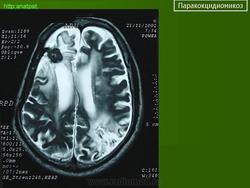

ГМ. Паракокцидиомикоз. +

Паракокцидиомикоз.

Множественные "узловые образования" имитирующие метастазы.